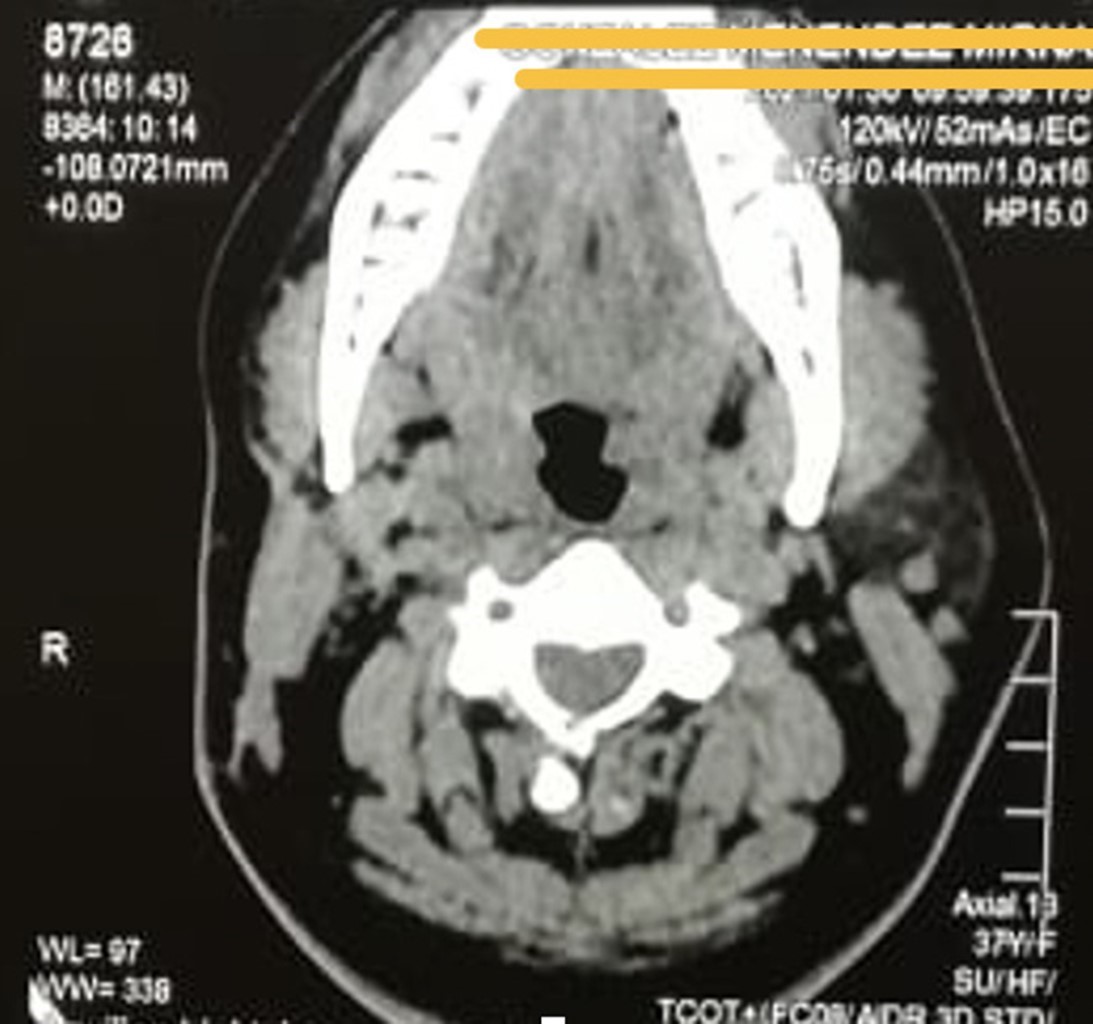

Figure 1

Figure 2

Figure 3

Figure 4

Figure 5

Figure 6

Figure 7

Figure 8

Figure 9

Figure 10

Figure 11

Figure 12